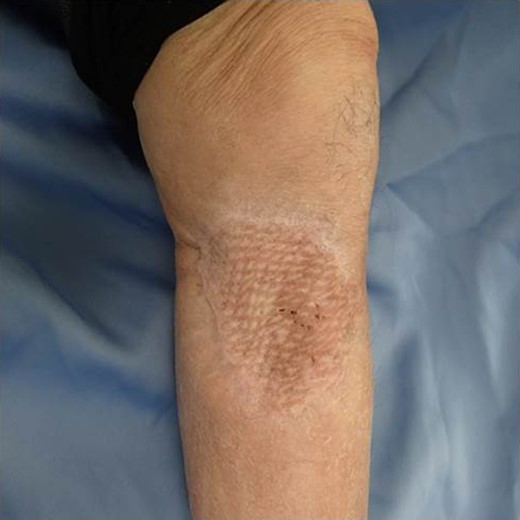

The patient was an 83-year-old male with a granulomatous tumor on his left lower leg. He said that it had existed for about 10 years. An incisional skin biopsy was performed at a neighbor medical institution and histopathologically suggested PCACC. He was introduced to our out-patient clinic. At his admission, the tumor was about 4 cm in the diameter and showed a few red granulomatous nodules (Fig. 1). MRI revealed that the tumor infiltrated subcutaneous tissue but did not reach muscle and bone (Fig. 2). The whole-body PET-CT showed that fluorodeoxyglucose (FDG) accumulated at the tumor area of the left lower leg. FDG also accumulated in the left inguen, however any other accumulation was not defected (Fig. 3). Therefore, it was suspected that the left inguinal hot spot was the metastatic lesion from the PCACC lesion at the left lower leg. At the first operation, the tumor was resected 2 cm far from the tumor margin, including basal muscle fascia and periosteum, and the defect was covered with an artificial dermis under general anesthesia (Fig. 4). At the same time, inguinal lymph node dissection was performed. Histopathological examination of the tumor revealed that cubical cells which had high nuclear-to-cytoplasmic ratio proliferated with cribriform, tubular or cord-like structure in the dermis and subcutaneous tissue. Perineural invasion by the tumor was observed. Metastasis to superficial inguinal lymph node was also histological confirmed (Figs 5 and 6). Most lumens had mucus which was stained by Alcian-blue (AL-B) and Periodic acid-Schiff (PAS) inside of them (Fig. 7). In the immunohistochemical findings, the tumor cells were positive for EMA, SMA, S-100protein, BerEP4, p63 and C-kit (Fig. 8). According to these clinical and pathological findings, the tumor was finally diagnosed the tumor as PCACC. Microscopically, the tumor was resected completely.

After one week from the first operation, the artificial dermis was removed because of much exudate and contamination of the wound. Since then, we washed it with saline every day. After one month from the first operation, it became clear, however, little granulomatous. So, we started negative pressure wound therapy to grow up the granulomas for 3 weeks. After two months from the first operation, wound bed preparation accomplished, and we performed additional resection with 1-cm resection margin and covered the defect by mesh skin graft which was taken from right inguen and thinned to 25/1000 inch (Fig. 9). The skin completely engrafted and no recurrence of the tumor was noted as of 1 year postoperatively (Fig. 10).